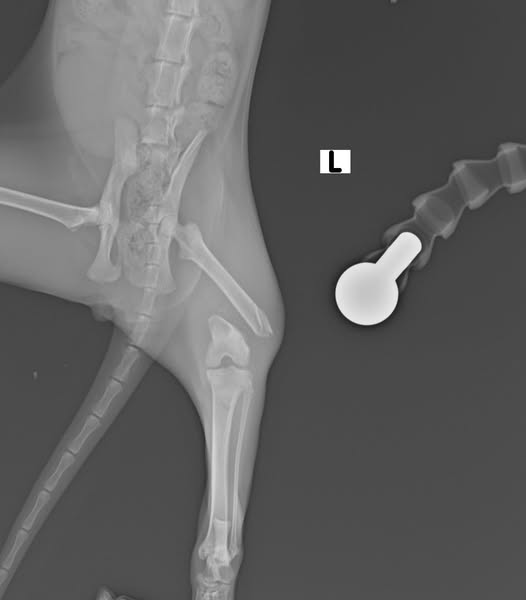

პოსტს თან ახლავს ოპერაციამდე და ოპერაციის შემდგომი რენტგენოგრაფიული გამოსახულებები, რომლებიც ხაზს უსვამს ქირურგიული ჩარევის შედეგად მიღწეულ შესანიშნავ პროგრესს. 1 თვის შემდეგ გაკეთებული რენტგენოგრაფია აჩვენებს ბარძაყის მოტეხილი ძვლის გამოსწორების და სტაბილიზაციის მნიშვნელოვან გაუმჯობესებას, რაც გუკუს შემთხვევის წარმატებულ შედეგს ადასტურებს 🩵

At the Agricultural University of Georgia’s Clinic Vetinarium, a kitten named Guku was diagnosed with a distal femoral fracture classified as 33A3 type. This classification indicates a complex, multifragmentary fracture of the distal femur.

Attached to this post are preoperative and postoperative radiographic images that highlight the remarkable progress achieved through surgical intervention. The 1-month postoperative images demonstrate significant improvement in the alignment and stabilization of the fractured femur, marking a successful outcome for Guku’s case 🩵